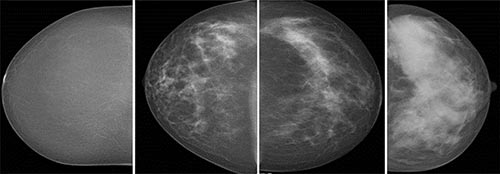

Researchers using automated breast density measurements have found that women with mammographically dense breast tissue have higher recall and biopsy rates and increased odds of screen-detected and interval breast cancer, according to a large new study from Norway published in Radiology.

For the new study, Dr. Hofvind and colleagues used automated software to help classify mammographic density in 107,949 women ages 50 to 69 from BreastScreen Norway, a national program that offers women screening every two years. The researchers looked at a total of 307,015 digital screening examinations that took place from 2007 to 2015.

The automated software classified breasts as dense in 28 percent of the screening examinations. Rates of screen-detected cancer were 6.7 per 1,000 examinations for women with dense breast tissue and 5.5 for women with non-dense breasts. Interval breast cancer, or breast cancer detected between screenings – usually by palpation – was 2.8 per 1,000 in the dense breast tissue group and 1.2 for women with non-dense tissue.